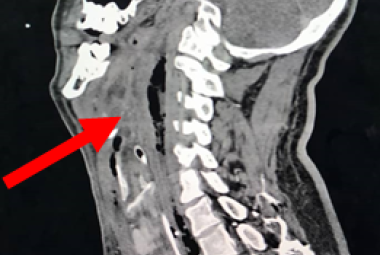

FIGURE 1: (A) Non-contrast CT brain demonstrated acute focal hemorrhage at the right occipital lobe withperihemorrhagic hypodensity extending to the right parieto-occipital region; (B) Subsequent CT venography in axial plane revealed thin linear isodensity within the right transverse sinus; (C) CT venography in coronal plane confirmed the filling defect within the right transverse sinus, consistent with thrombus